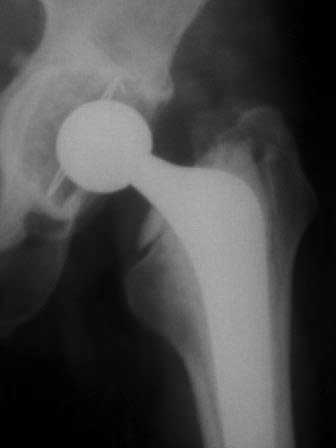

ниже снимок в 2008 году

далее снимок в 2009 году

далее снимок у меня на приеме

Пациент 60 лет, мужчина. Оперирован в 2007 году, поочередно оперированы два тазобедренных сустава с интервалом в 4 месяца. В 2008 году оперирован на сердце(аорто-коронарное шунтирование).Операция осложнилась инфицированием операционной раны в области грудины, лечился в гнойном отделении.

В конце 2008 года отметил боли в правой паховой области при опоре на правую ногу. На рентген снимках таза с тазобедренными суставами явных признаков нестабильности вертлужного компонента не обнаружено. В 2009 году нейрохирурги его "успешно" прооперировали на L\3-\4 связывая болевой синдром в правой паховой области с наличием грыжи указанного межпозвонкового диска. Состояние только ухудшилось, больной уже не мог долго сидеть, боль прогрессировала . Его в 2009 и 2010 годах смотрел ортопед, делались рентгенснимки, но почему то приходили к выводу что эндопротез справа стабилен. В марте 2011 года я впервые увидел его, через одну неделю после этого был прооперирован. На операции вертлужный компонент при упоре на него инструментом прокручивался во впадине и без труда был извлечен.

Эндопротез Ножка Cerafit компании Ceraver- чашка той же компании.

Расшорошили вертлужную впадину (дебридмент) Заменили чашку,учитывая невозможность полностью исключить инфекционный генез нестабильности, установили вертлужный компонент цементной фиксации (цемент с ванкомицином), поменяли головку из-за изменившихся взаимоотношении между бедренным компонентом и новой чашкой. Рану зашили наглухо. Провели антибактериальную терапию Кубицином. Выписали на 10 сутки после операции. Болевой синдром купирован, пациент радостный, уехал к себе в Калугу. Приедет на контрольный осмотр через месяц.